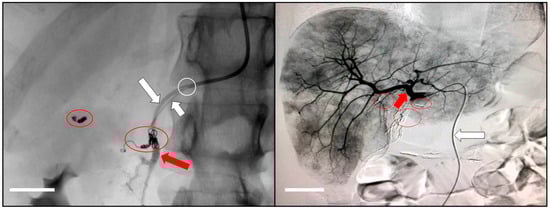

- Chevallier, O.; Mvouama, S.; Pellegrinelli, J.; Guillen, K.; Manfredi, S.; Ghiringhelli, F. Percutaneous Implantation of a Microcatheter-Port System for Hepatic Arterial Infusion Chemotherapy of Unresectable Liver Tumors: Technical Feasibility, Functionality, and Complications. Diagnostics 2021, 11, 399. [Google Scholar] [CrossRef]

- Favelier, S.; Germain, T.; Genson, P.Y.; Cercueil, J.P.; Denys, A.; Krausé, D.; Guiu, B. Anatomy of liver arteries for interventional radiology. Diagn. Interv. Imaging 2015, 96, 537–546. [Google Scholar] [CrossRef]

- Deschamps, F.; Rao, P.; Teriitehau, C.; Hakime, A.; Malka, D.; Boige, V.; Ducreux, M.; Elias, D.; Goere, D.; de Baere, T. Percutaneous femoral implantation of an arterial port catheter for intraarterial chemotherapy: Feasibility and predictive factors of long-term functionality. J. Vasc. Interv. Radiol. 2010, 21, 1681–1688. [Google Scholar] [CrossRef]

- Herrmann, K.A.; Waggershauser, T.; Sittek, H.; Reiser, M.F. Liver intraarterial chemotherapy: Use of the femoral artery for percutaneous implantation of catheter-port systems. Radiology 2000, 215, 294–299. [Google Scholar] [CrossRef]

- Tanaka, T.; Arai, Y.; Inaba, Y.; Matsueda, K.; Aramaki, T.; Takeuchi, Y.; Kichikawa, K. Radiologic placement of side-hole catheter with tip fixation for hepatic arterial infusion chemotherapy. J. Vasc. Interv. Radiol. 2003, 14, 63–68. [Google Scholar] [CrossRef]